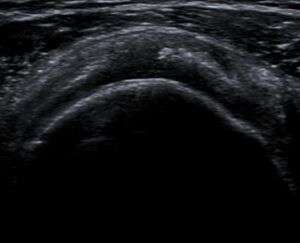

La ecografía juega un rol fundamental en el diagnóstico de la tendinopatía cálcica. Permite la caracterización de las calcificaciones, incluyendo la forma, tamaño y morfología. A diferencia de la radiografía, la ecografía tiene mejor correlación con las fases de la tendinopatía cálcica, y por ende mejor correlación con la sintomatología. En la fase de reposo, las calcificaciones presentan un arco ecogénico bien definido asociado a sombra acústica posterior, mientras que en la fase reabsortiva se presentan menos definidas, con morfología polimorfa, con sombra acústica parcial o ausente. En este caso, en eco se ve una imagen lineal ecogénica con sombra posterior (calcificación) en el tendón supraespinoso.